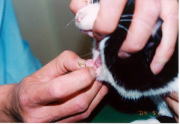

�ȉ��@��p�O�̎ʐ^�A�A��p��̎ʐ^�ł��B

�_���ň͂����������A��ᇂ��������ꏊ�ɂȂ�܂��B�����ň͂������ʂ��ȉ~�`���؏����ʂɂȂ�܂��B

�ȉ��@��p�O�̎ʐ^�A�A��p��̎ʐ^�ł��B

�@��p�O�̎ʐ^�ł��B

��p�O�ɁA�Ö@���s���Ă��܂��̂ŁA�����ڏ��ᇂ́A���������悤�Ɍ����܂����A���ۂɐG�f���Ă݂�Ǝ�ᇂ̐c�̂悤�Ȃ��̂��A�܂��A�c�����Ă��܂��B�i�Ö@�𒆎~����ƁA�܂��A���ɖ߂��Ă��܂��܂��B�j�_���ň͂����������A��ᇂ��������ꏊ�ɂȂ�܂��B�����ň͂������ʂ��ȉ~�`���؏����ʂɂȂ�܂��B

�A��p��̎ʐ^�ł��B

�I�̔畆����̕��ֈڐA����Ă��܂��B���̎�p�̏ꍇ�A�_�o�A��Ö��Ƃ����_�o�E���ǂ�����܂��̂ŁA���������Ȃ��悤�Ɏ�p���s���܂��B�܂��A�ڐA��̔畆�̌��\���ǍD�ł��B